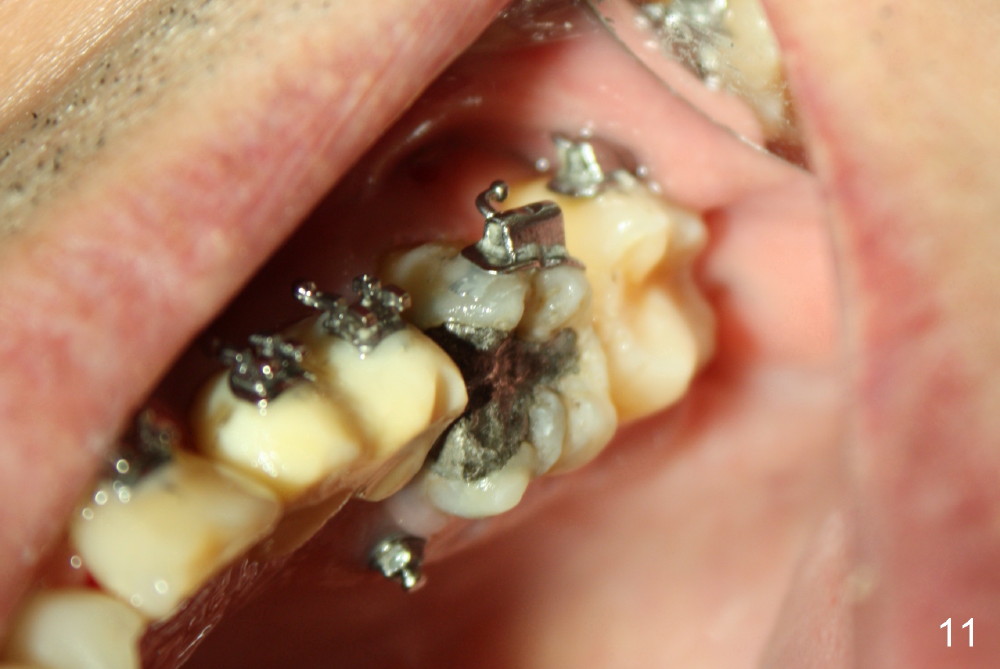

A 51-year-old man needs implants at the sites of #12,13,19 (Fig.1). The teeth #12 and 13 are extracted. An implant is placed at #19 (Fig.2 <). After osteointegration, an abutment is placed (Fig.2 A). The opposing tooth, #14, is found supraerupted. Two mini-implants are placed at the mesiobuccal and distolingual areas of #14 (Fig.3 (mirror view) <) and a power chain (*) is placed for intrusion. In the next 8 months, these 2 mini-implants become loose. Two new mini-implants are placed in the mesiolingual and distobuccal regions (Fig.4 ^). The one in the distobuccal region is loose after a while (Fig.6,7 >). In brief, mini-implants are not efficient in intrusion. At this time, the implants at the sites of #12,13 apparently osteointegrate (3 months post placement) and abutments are placed (Fig.4). Provisional crowns are fabricated (Fig.5). Brackets are placed between #11 and 15 with the bracket at #14 placed more coronally than those of the neighboring teeth (Fig.6-8). Mesially there are two excellent anchorages (#12,13) as well as the mesiolingual mini-implant. The distal anchorage is #15. In the next 5.5 months, the tooth #14 is intruded (Fig.9,10), but the 2nd molar is mobile (not as strong as #14). A longer mini-implant is placed in the distobuccal corner (>, more apical than before (Fig.7)). The distobuccal mini-implant is found to be mobile in 3 weeks (Fig.11). It appears that there is enough clearance for restoration of #19 (Fig.12). Power chains are placed between the mesiolingual mini-implant and #14 buccal tube until the appointment for crown prep. In this way, the lingual cusps may ascend (Fig.13 red arrow), while the buccal ones may descend (black arrow). The occlusal clearance will be more favorable.